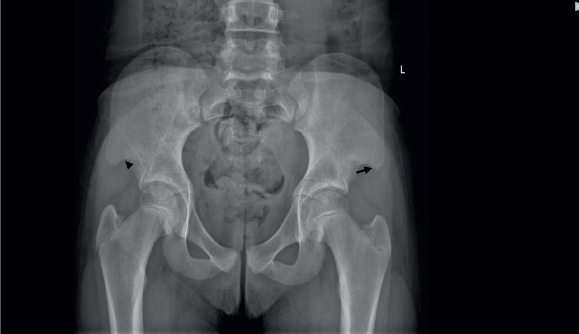

The father of this 11-year-old girl has the same disease. The pelvic X-ray of the child (Figure 1) demonstrates a pathognomonic feature of the underlying disease.

NPS is a rare genetic autosomal dominant disorder, characterised by hypoplastic nails and patellae, and the presence of a bilateral extra piece of iliac bones on both sides ‘iliac horns’ in pelvic X-ray [14]. The image in our case (Figure 1) clearly shows ‘posterior horns’ of both iliac bones where the posterior aspects of both iliac bones are not even or straight, they are curved and appear like ‘horns’ (Figure 1, arrows), the presence of which is pathognomonic of this rare disorder [14]. The child had other features of the disease such as scoliosis and hypoplastic thumb nails. Both patellae were mildly hypoplastic and the right patella was displaced laterally (genu varum) (Figure 2, arrows).

Figure 1. A pathognomonic feature of the underlying disease (see below).